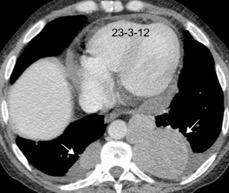

Hepatoesplenomegalia

Riñones poliquísticos

Ascitis masiva

Carcinomatosis peritoneal

Elevación bilateral por riñones poliquísticos. Hernia hiatal ¡Sin gas en abdomen!